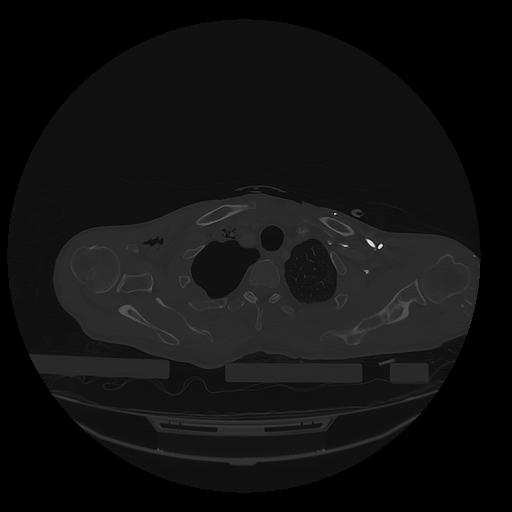

31 PULMON,CE,Vol,1.0,PULMON,,